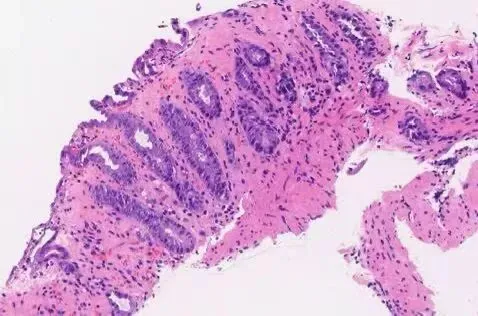

3:缺血性结肠炎:固有层玻璃样变,隐窝上皮呈非典型性改变:细胞核深染,核增大。

组织学形态

固有层:玻璃样变(透明变),正常疏松结缔组织被致密嗜酸性基质替代,可见浆细胞、淋巴细胞、嗜酸性粒细胞浸润,伴固有层崩解

细胞学:非典型性改变(染色质浓染、核增大、异常核分裂象等)